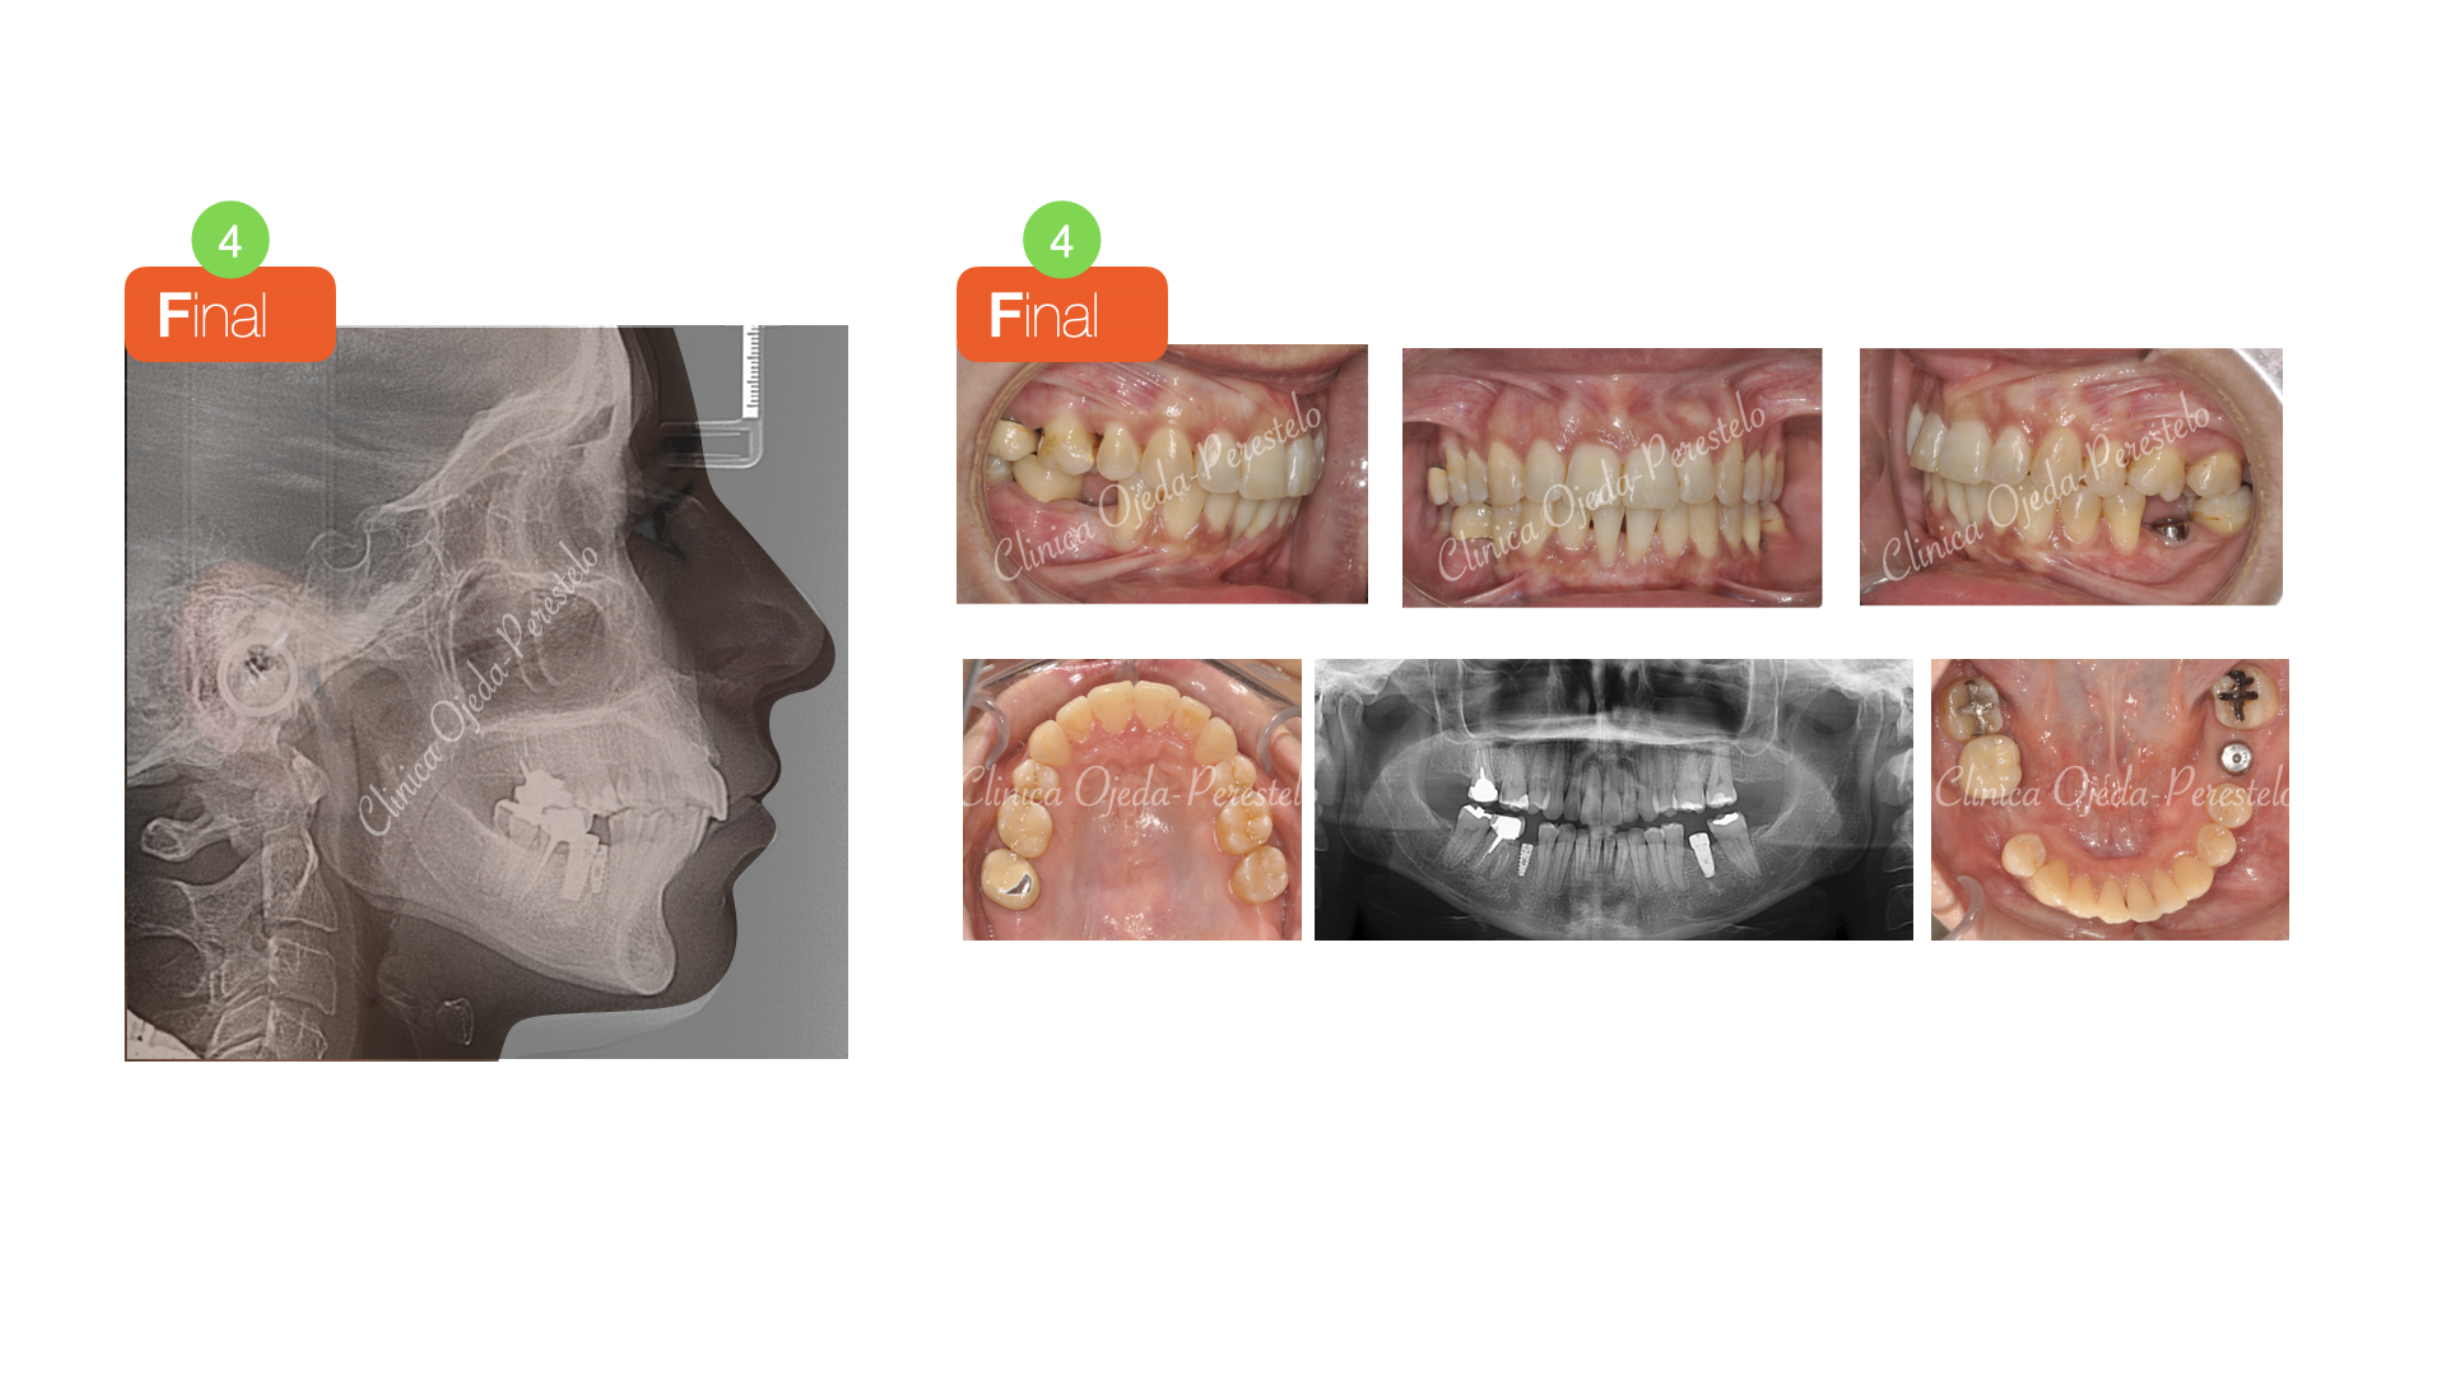

Clase II ósea con Resalte muy Aumentado y Extracciones dentarias

Paciente tratado con brackets de autoligado pasivo (Sistema Damon) donde hemos alineado, nivelado y expandido las arcadas. Además hemos realizado las extracción del primer premolar superior izquierdo ( ya la paciente presentaba extracciones de las piezas 25,45,36 ) para solucionar el gran Resalte presente. La paciente no quería realizarse cirugía ortognática.

Quisieramos destacar cómo las extracciones de premolares no necesariamente comprimen la arcada ni empeoran la amplitud de la sonrisa. La paciente se encuentra en la actualidad pendiente de colocarse sus coronas sobre implantes.